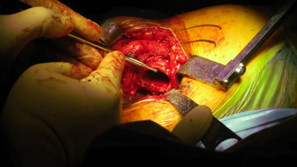

First case was a 47-year-old small female with mechanical impingement, torn labrum, and over 30% delamination of acetabular articular cartilage. There was also concern as to the sizing, that it might be too small for the size 1 ARC stem with a socket size of 46 mm.

| Posterior approach. |

| Initial femoral neck resection high retained most of the neck. |

| Very tight on the reaming was going to push the limit on sizing for this patient. |

| Small Ben Hur was used to open for the ARC Awl. |

Rat tail rasp was then used as both a canal finder and to slightly enlarge the opening. This worked fairly well. |